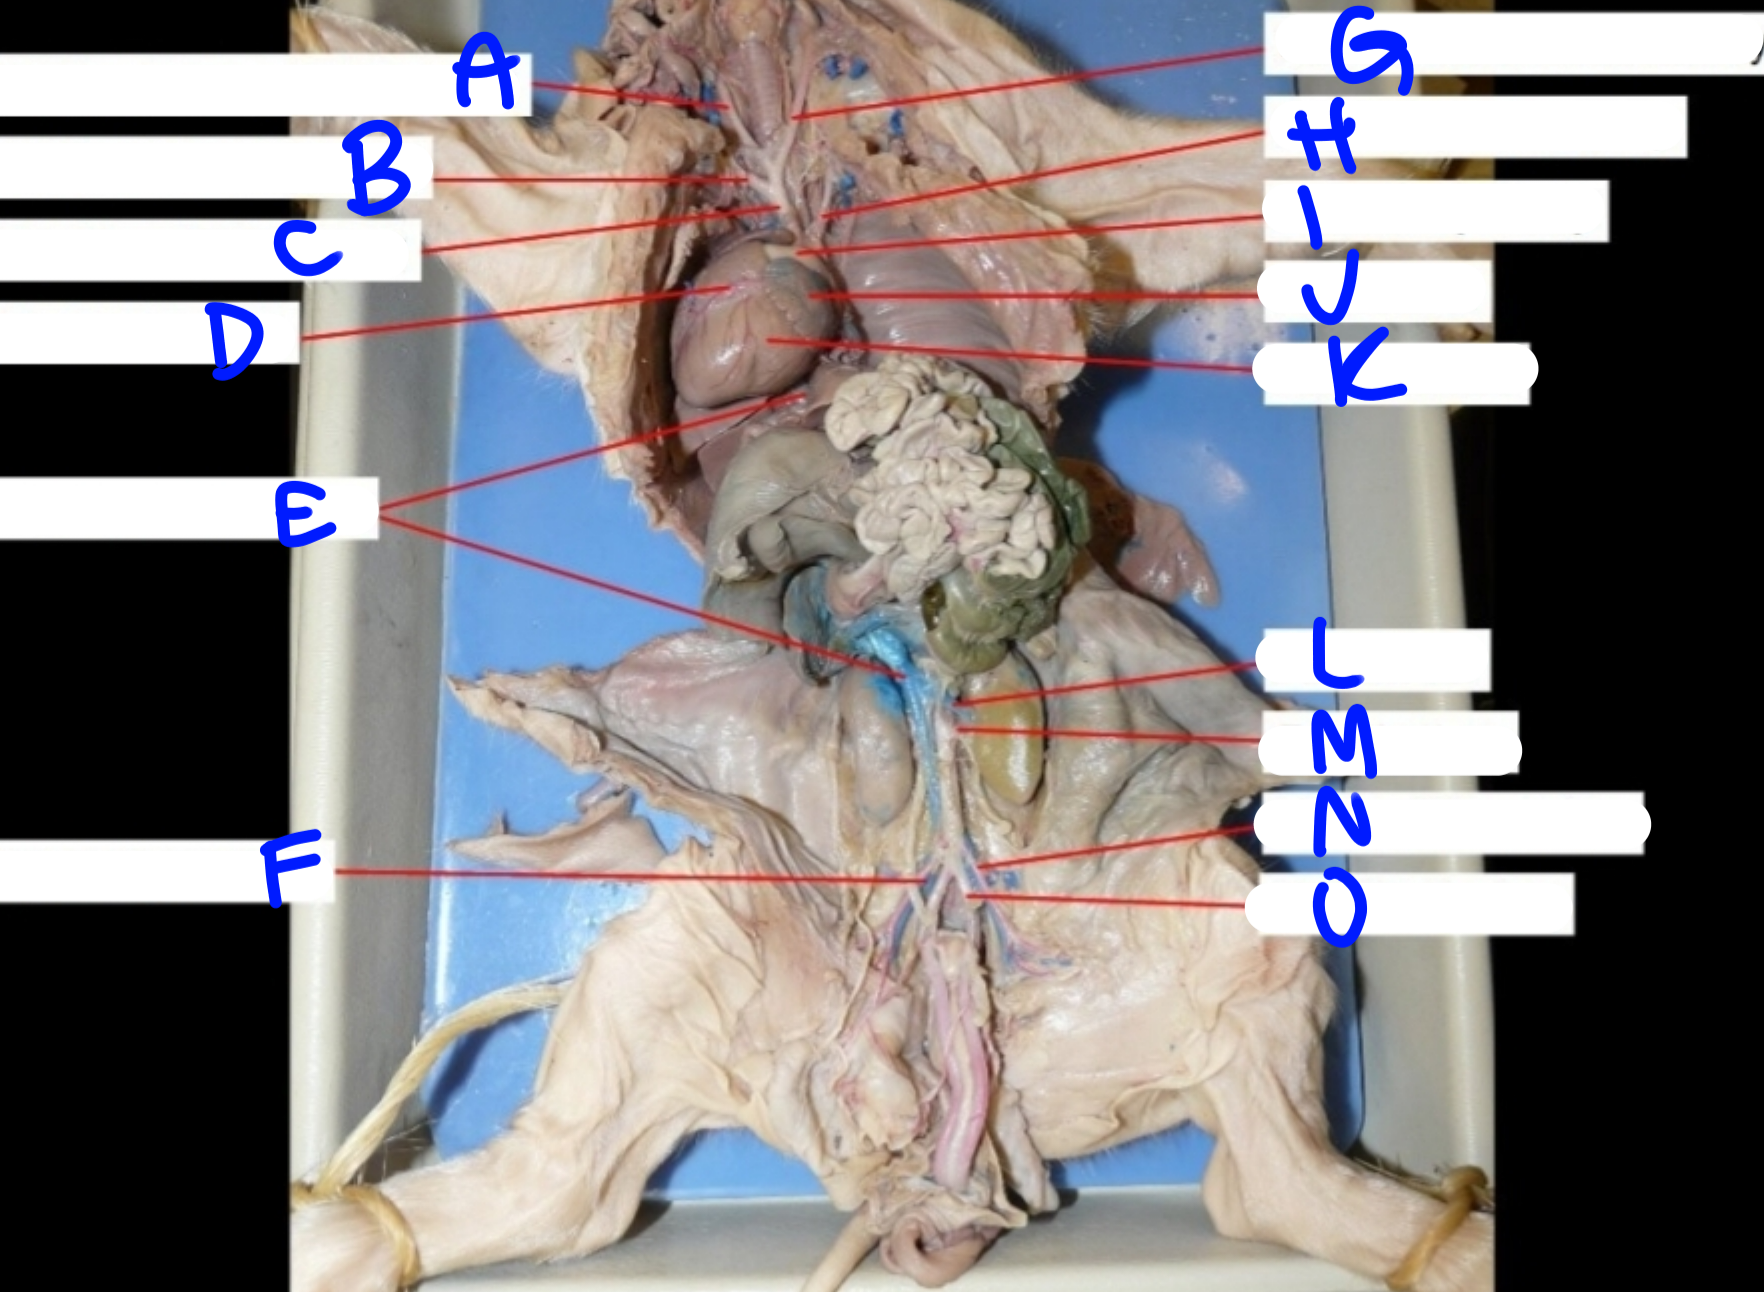

A

Right common carotid artery - delivers oxygenated blood to the head & neck

B

Right subclavian artery - delivers oxygenated blood to the upper body

C

Brachiocephalic artery - delivers oxygenated blood to the upper body

D

Coronary artery - delivers oxygenated blood to the heart

E

Posterior vena cava - carries deoxygenated blood from the lower body to the right side of the heart

G

Left common carotid artery - delivers oxygenated blood to the upper body

H

Left subclavian artery - carries oxygenated blood to the upper body

I

Pulmonary artery - delivers deoxygenated blood from the heart to the lungs

J

Left atrium - delivers oxygenated blood to the left ventricle

K

Left ventricle - delivers oxygenated blood to the systemic circuit

L

Renal vein - delivers blood from the kidney & ureter to the inferior vena cava

M

Renal artery - delivers blood from the kidney & ureter to the inferior vena cava

O

Umbilical artery - carries deoxygenated blood to the placenta